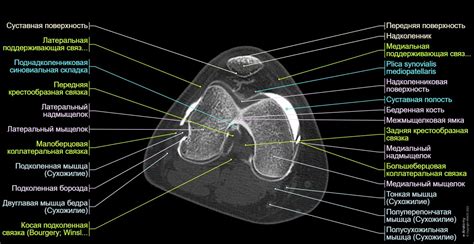

Колено КТ-артрография : нормальная анатомия | e...